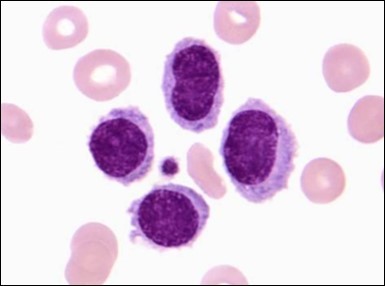

The classic hairy cell is medium sized with a magnitude of 10-14µm. The moderately abundant or variable cytoplasm may be transparent or mildly basophilic. The cellular surface with the characteristic serrated perimeter depicts innumerable fragile or stout extensions of cytoplasm ,particularly discernible on the phase contrast and electron microscopy. The cytoplasm may exhibit vacuoles with occasional azurophilic granules4. The nucleus may be elliptical or reniform, folded or indented with a coarse, reticulated or a finely dispersed chromatin and inconspicuous nucleoli along with infrequent mitosis. Bone marrow aspiration or bone marrow trephine biopsy may be inadequate for diagnosis in 30%-50% individuals4. The trephine sections of the bone marrow may depict a characteristic interstitial pattern of leukaemic infiltration. Generally the bone marrow is hyper-cellular, though it may be hypo-cellular in 10-15% individuals4. The leukaemia cell ingress may be diffuse or partial, although diffuse infiltration is frequent. The partial variety of leukaemic dissemination may be ineptly categorized with an indeterminate differentiation from the uninvolved marrow. The malignant insertions may initially emerge as miniature, undefined, cellular loci. The formalin fixed, paraffin embedded sections may elucidate a crystalline zone or a “halo” appearance of the cells with a circumscribed nucleus on account of the plentiful cytoplasm4. The cellular margins may be intertwined. Fixation of bone marrow smears with Zenker’s fixative may demonstrate a retracted cytoplasm of the hairy cells with a consequent disconnected structure. The bone marrow in the absence of a malignant process may be hypo-cellular or hyper-cellular. Reticulin stains may delineate an enhanced accrual of broad, dense reticulum fibres surrounding the aggregates of leukaemia cells with the fibrous circumlocution of individual malignant cell and fibrotic extensions into the abutting, uninvolved bone marrow4.

The leukaemia cells may enunciate a characteristic immune phenotype, crucial for a confirmatory diagnosis. The peripheral blood mononuclear B cell population may display a kappa or lambda light chain restriction. The phenotype of classic hairy cell leukaemia may be delineated by concurrent, immune reactive CD19+ CD20+,CD 11c+, CD25+, CD103+ and CD123+. An intensely immune reactive CD200+ and a non reactive CD27- antigen may be present2, 4. Evaluation of a trephine bone marrow biopsy and bone marrow aspirate may define the degree of tumour infiltration. A dry tap on account of prominent bone marrow fibrosis may be elucidated at preliminary diagnosis. A decline in the normal haematopoiesis may account for a hypo-cellular marrow in 10% instances. Gradation of cellular infiltrating of the leukaemia within the bone marrow may be appropriately investigated with immune –histochemical stains2, 4. Immune staining for CD20+, annexin 1 and VE1 (a BRAF V600E stain] may validate the diagnosis and precisely analyse the extent of malignant bone marrow infiltration[8]. Determination of BRAF V600E mutation may be critical in therapeutically non responsive individuals with applicable standard therapy or in instances of multitudinous reoccurrences[9]. Deploying inhibitors of BRAF V600E gene may be efficacious in patients impervious to approved therapy. The mutation necessitates a comprehensive scrutiny of the implicated individuals with a sensitive molecular assay which may discern up to < 10% of the hairy leukaemia cells appearing in the peripheral blood smears or bone marrow aspirates diluted with peripheral blood or aspirates elucidating a dry tap[2,4]. Allele specific polymerase chain reaction (PCR) or a next generation sequencing may be optimally employed to circumvent false negative outcomes. If the leukaemia cells are sparse or if particularly sensitive & efficacious molecular techniques are not accessible, the application of appropriate immune histochemical stains to the bone marrow biopsy such as a BRAF V600E mutation stain (VE1) may detect the hairy cells and conclusively diagnose the condition[2,4,10]. Figure 1, Figure 2, Figure 3, Figure 4, Figure 5, Figure 6, Figure 7, Figure 8, Figure 9, Figure 10, Figure 11, Figure 12, Figure 13, Figure 14.

Figure 10.HCL: inconspicuous nucleoli, open-ended chromatic and surface protrusions(26).

Figure 11.HCL Oral mucosa with soft tissue infiltration of hairy cells(27).

Figure 12.HCL: hairy cells with broad and fine projections of the cytoplasm(28).